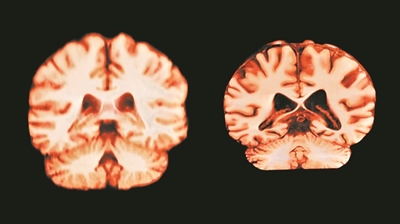

健康大脑(左)和受阿尔茨海默病影响的大脑。

图片来源:英国《自然》杂志网站

了解健康大脑的自然老化规律,有助于更好地认识神经退行性疾病的发展机制。若阿尔茨海默病与这些变化相关,应当能在女性的海马体和楔前叶等关键区域中观察到更快的萎缩,但研究未发现这种现象。阿尔茨海默病的成因复杂,仅凭年龄相关的脑萎缩不足以揭示其机制。